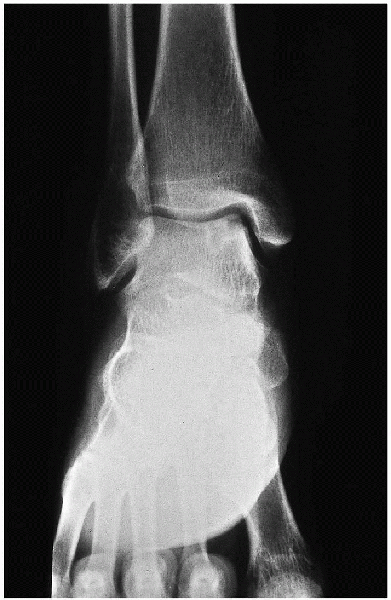

![]() |

FIGURE 31-9. Osteochondral lesion on the medial aspect of the talus.

of chondral and osteochondral lesions of the ankle (i.e.,

loose bodies (Figs. 31-9, 31-10, 31-11 and 31-12).